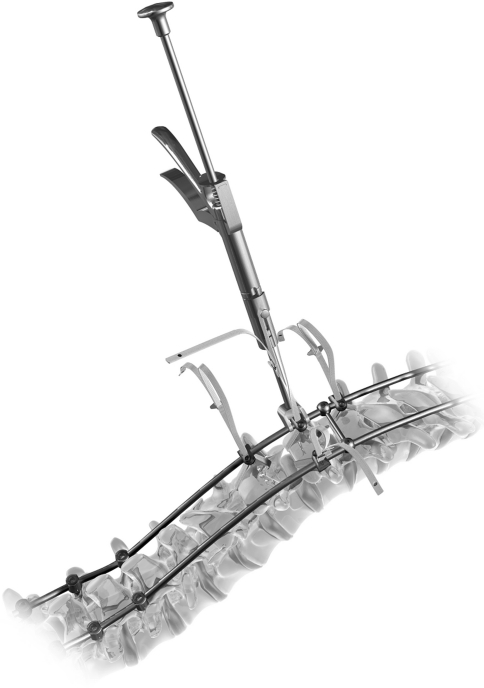

The Universal Clamp is a novel implant used in place of sublaminar wiring, pedicle screws, or hooks to bind vertebrae to fusion rods in spinal osteosynthesis. The UC consists of three components, a woven polyester band (Dacron), a titanium alloy (or stainless steel) clamp, and a locking screw (Ti alloy or stainless steel) (Fig. 1).

Fig. 1.

The Universal Clamp

The UC technique is similar to the Luque technique, but sublaminar polyester bands are used instead of sublaminar wiring. The surface area of contact between the polyester band and lamina is larger than that between wiring or cables and the lamina permitting application of greater spinal deformity reduction forces without laminar fracture. The deformity reducing forces are applied progressively, step-wise at one or more spinal segments with a reduction tool that is activated in the same simple manner as a rongeur. The clamp connects the sublaminar band to the rod. The strength of the band-rod connection is equivalent to screw-rod or hook-rod connections permitting conventional deformity correction maneuvers including translation, compression/distraction, and in situ bending.

Once all Universal Clamp implants are placed along the spine and the prebent double-rod frame has been anchored to pedicle screws at the distal end of the construct, each UC is placed on the appropriate rod. The upper jaw of the clamp is closed over the rod.

The locking screw is loosely inserted to leave the band free to permit traction of the vertebrae toward the rod with the reduction tool (Figs. 2, 3). After any reduction maneuvers and once optimal band tension has been obtained, the clamp is locked onto the rod with the screw. The loop of band is removed from the reduction instrument and the excess band strands (including the malleable insert and the metal buckles) are cut and removed.